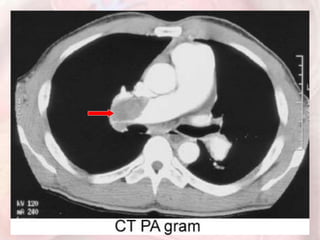

CT angiography (CTA), using a multidetector

spiral scanning system

•primary diagnostic method for suspected PE

•the sensitivity and specificity for detection PE > 90%

•provide clues to possible alternative diagnoses in

patients with symptom consistent with PE

BUT…

•Dye load and large radiation dose